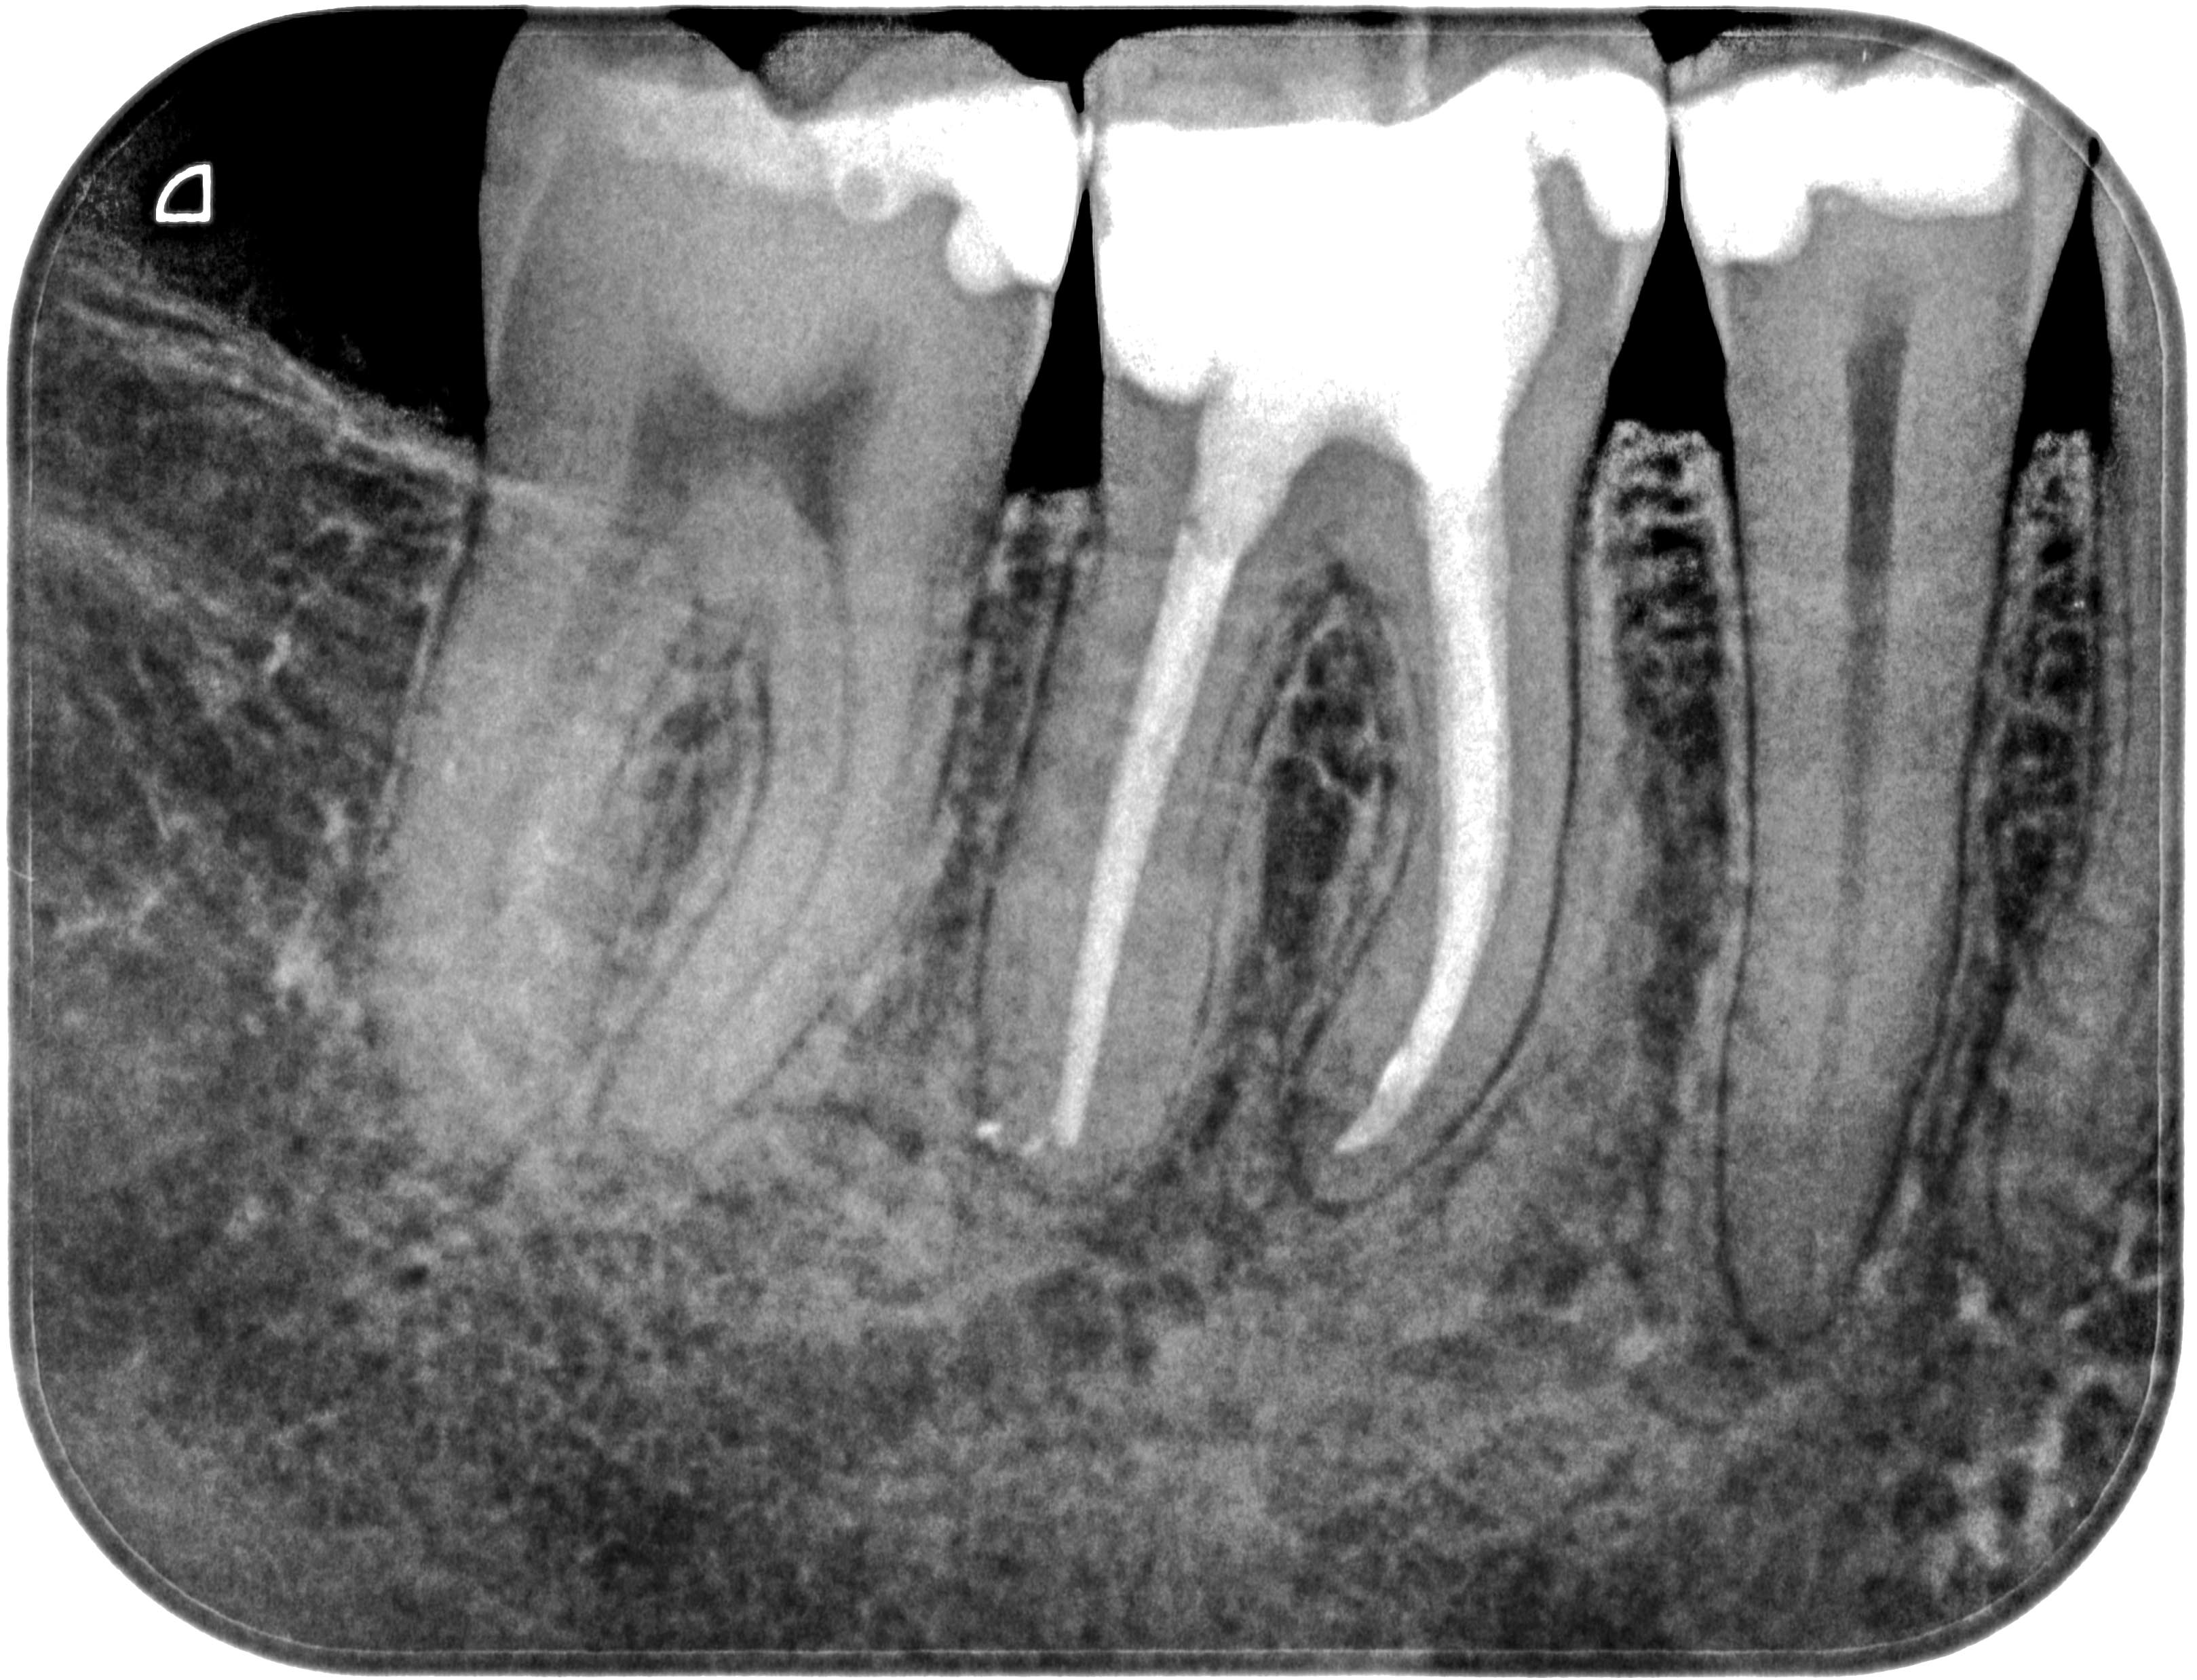

WS46 (3 von 4) Veröffentlicht 21. März 2016 am 3238 × 2476 in Calciumhydroxid- Überpressung (2) 18. September 2013